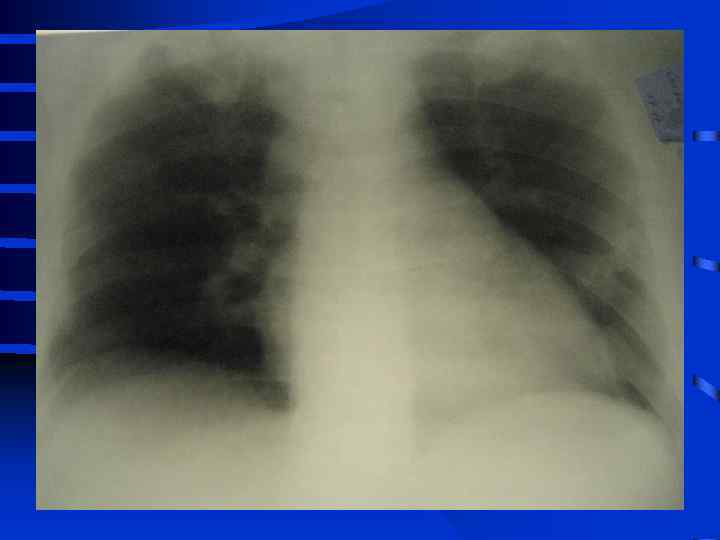

• IV стадия появляются симптомы присоединения инфекции с развитием гнойного трахеобронхита и пневмонии (госпитальной), признаки сепсиса, вторая волна полиорганной недостаточности. Индекс оксигенации менее 100, появляется гиперкапния. Рентгенографически - резкое снижение прозрачности легочных полей, множественные хлопьевидные тени (“снежная буря”).